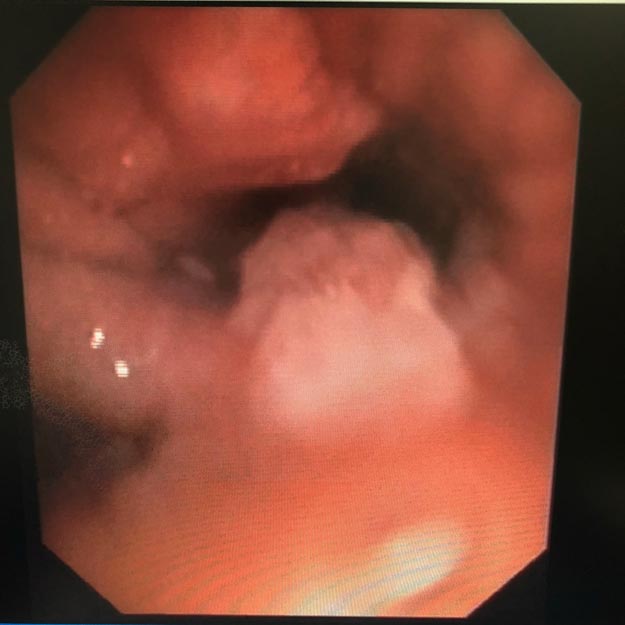

(陈阿姨增生的肉芽) 于是,呼吸内科医师决定再给陈阿姨做进一步的镜下治疗。在广州市第一人民医院呼吸科主任赵子文教授的指导下,市工人医院成功完成了第一例纤支镜球囊扩张术。经过规范的抗感染和纤支镜下介入治疗,陈阿姨最终康复出院。

(纤支镜球囊扩张术)

(纤支镜球囊扩张术)发现支气管异物应及时就医